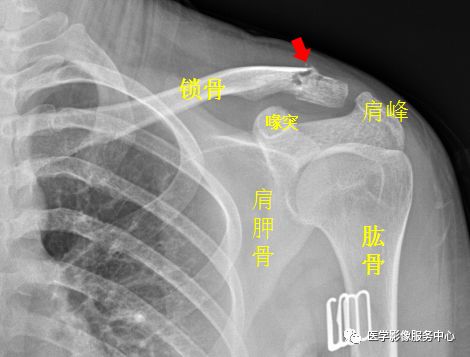

左侧锁骨肩峰端见不规则透亮线,骨折处稍移位。左侧锁骨骨折。